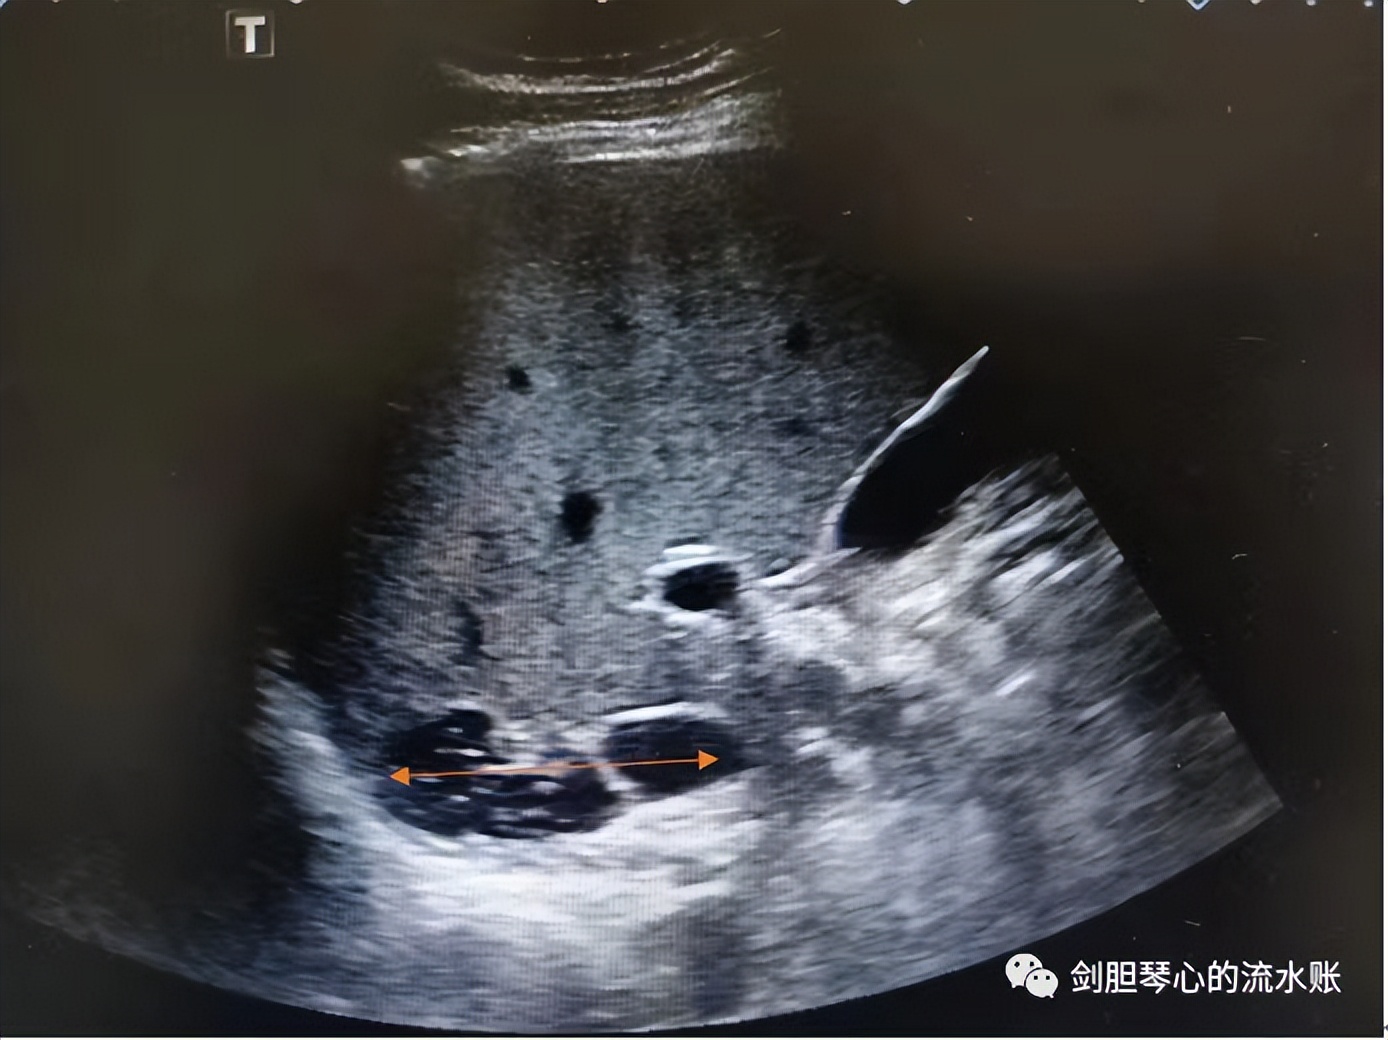

超声:右侧肾上腺区,紧邻下腔静脉可见混合回声区,大小56mm*24mm,边界清晰,内部回声不均匀。